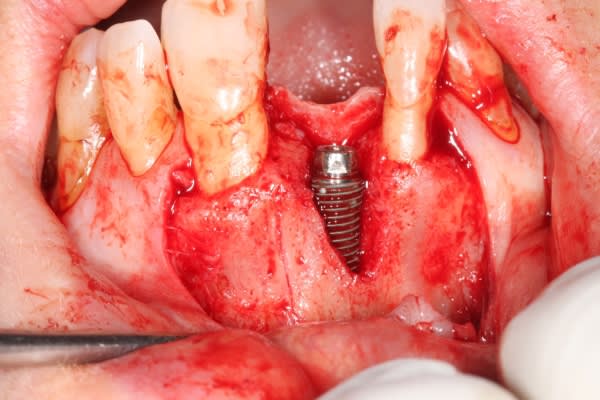

dans cette technique un pilier de 2mm de haut est vissé sur l'implant, ce pilier contient un orifice qui permet de transfixer la barre (photo 3,4)

l'espace créé est rempli avec un biomat et le tout est recouvert d'une membrane